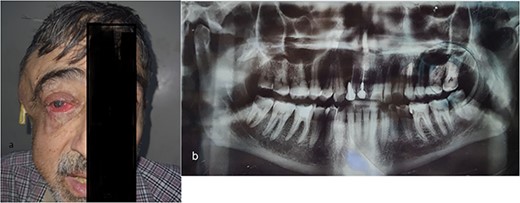

The patient was referred to the emergency room of a hospital in Damascus. The oral and maxillofacial team requested a panoramic dental X-ray (Fig. 1b). The patient was given Ceftriaxone, Carbapenem and Amikacin according to the outcome of the bacterial culture and antibiotic sensitivity test, which revealed Enterobacter. The pus was obtained by needle aspiration of the buccal space. To drain the abscess, an oral cavity’s right buccal and right temporal incisions were made, and a corrugated drain was inserted in both incisions. Despite treatment within a week, the swelling got worse and the right eye’s visual acuity started to deteriorate.

(a) The right masticatory, buccal and temporal regions are markedly swollen, and a drain has been inserted into the abscess cavity in temporal region. There is obvious pus oozing from the right eye, and the right eyelid and cornea both exhibit redness and edema. (b) Panoramic radiograph revealed periapical abscess, lateral large deep caries with pulp involvement in the third right mandibular molar tooth.